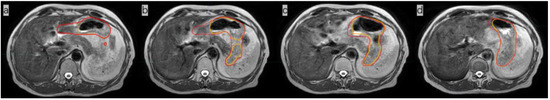

A 70-year-old female patient presented with anorexia in September, 2021. A gastroscopy showed a 5*5 cm bulge in the middle curve of the gastric body. FDG-PET/CT showed a high FDG-avid gastric mass with slightly FDG-avid lymph nodes. The pathology report showed an extra-lymph node marginal zone indicative of a MALT lymphoma. Immunohistochemistry to measure biomarkers showed the following results: CD20+, CD79a+, CD3-, CD7-, CD5-, CD10-, BCL-6-small amount+, BCL-2 partial+, Mum-1-, C-Mum-1-, C-myc-, CyclinD1-, P53+ about 60% and Ki-67+ about 10%. A bone marrow biopsy showed active bone marrow proliferation with no obvious lymphoma cell involvement. The patient was diagnosed with stage IIE gastric MALT lymphoma according to Ann Arbor staging. The patient received four cycles of rituximab and then ISRT on the whole stomach and the involved lymph nodes, administering ISRT at 30 Gy/15 fractions. The CTV included whole stomach and the enlarged metastatic lymph nodes and was expanded by 1 cm to generate the internal target volume (ITV) so to cover the stomach movement. CBCT was daily performed before radiotherapy to adjust the setup error. However, using daily on board CBCT imaging, we found that the stomach images were poor and did not allow carrying out the adaptive plan for this patient with gastric MALT lymphoma (Figure 5).

Figure 5.

Images of patient #2 with contrast CT simulation (a) and CBCT imaging (b). The red line in (a) shows the stomach, and the green line contours the PTV.

IGRT has become routine as a standard configuration in modern radiation therapy. Imaging the patient prior to treatment can help reduce the impact of setup errors, thus improving the dose delivery accuracy [13]. Currently, most modern radiotherapy systems are equipped with kV CBCT to visualize anatomical structures and identify the target volumes. Although CBCT is highly effective, it provides images with poor quality for soft tissues—including abdominal organs such as the liver, stomach, and pancreas—which makes it very difficult to accurately identify the soft-tissue targets and surrounding OARs. In the case of our gastric MALT lymphoma patient shown in Figure 5, it was not feasible to use CBCT for image guidance because of its poor image quality. A larger PTV margin with at least 1 cm had to be delineated, but this would cause higher toxicity to OARs. In addition, a 1 cm margin could not cover the entire empty stomach even if anisodamine (dose 10 mg) was administered to reduce gastric motility (Figure 4) [14] (pp. 174–177). As shown in Figure 4, even after expanding the PTV by 1 cm as usual with CBCT online guidance, there remain 8/15 axis planes that could not cover the entire stomach. Therefore, the target, i.e., the entire stomach, would be missed in regular clinical practice without MRI image guidance. Poor CBCT imaging of the stomach makes it more challenging to incorporate corrections for certain differences in routine patient anatomy, as well as to use approaches based on adaptive treatment protocols. The MR-LINAC system overcomes the limitations of traditional IGRT, especially for soft tissues requiring the precise definition of the target and of OARs. MR-LINAC improves IGRT by enhancing soft-tissue contrast in MR images without delivering concomitant radiation doses. MR-LINAC brings a unique emerging workflow that can help radiation therapy practitioners improve their skills and understand MR anatomy. The case reported here illustrates that MR-LINAC could visualize the stomach clearly, especially after administering anisodamine. Meanwhile, an attractive option for MR-LINAC might be to re-optimize or adjust the therapeutic plan before each radiation treatment. Diagnostic-quality MR images can be acquired based on the actual patient anatomy before and during treatment and then used in an online adaptive workflow. Compared to CBCT, online 1.5 T MRI provides better target visualization on an MR-LINAC and aids online adaptive treatment strategies, including daily replanning. Although online adaptation techniques guided by CBCT are improving, the quality of stomach images obtained by CBCT is likely to remain poor. In contrast, in MRI-guided therapy, increased soft-tissue contrast can more accurately visualize day-to-day variations and may allow the delineation of a smaller PTV margin, thus reducing OAR toxicity [15].